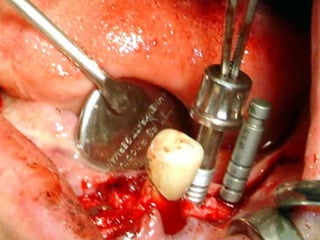

Plastia de maxilares para implantes dentales.

La conformación quirúrgica de un contorno alveolar adecuado es

determinante para la correcta aplicación y aceptación de los implantes

de titanio, aquí proponemos una técinica para lograr el espesor óseo

suficiente y la corrección estética del proceso, ya que antiguamente al

extraer un diente se acostumbraba presionar las tablas alveolares

“para cohibir la hemorragia”, con el colapso subsiguiente de la región.